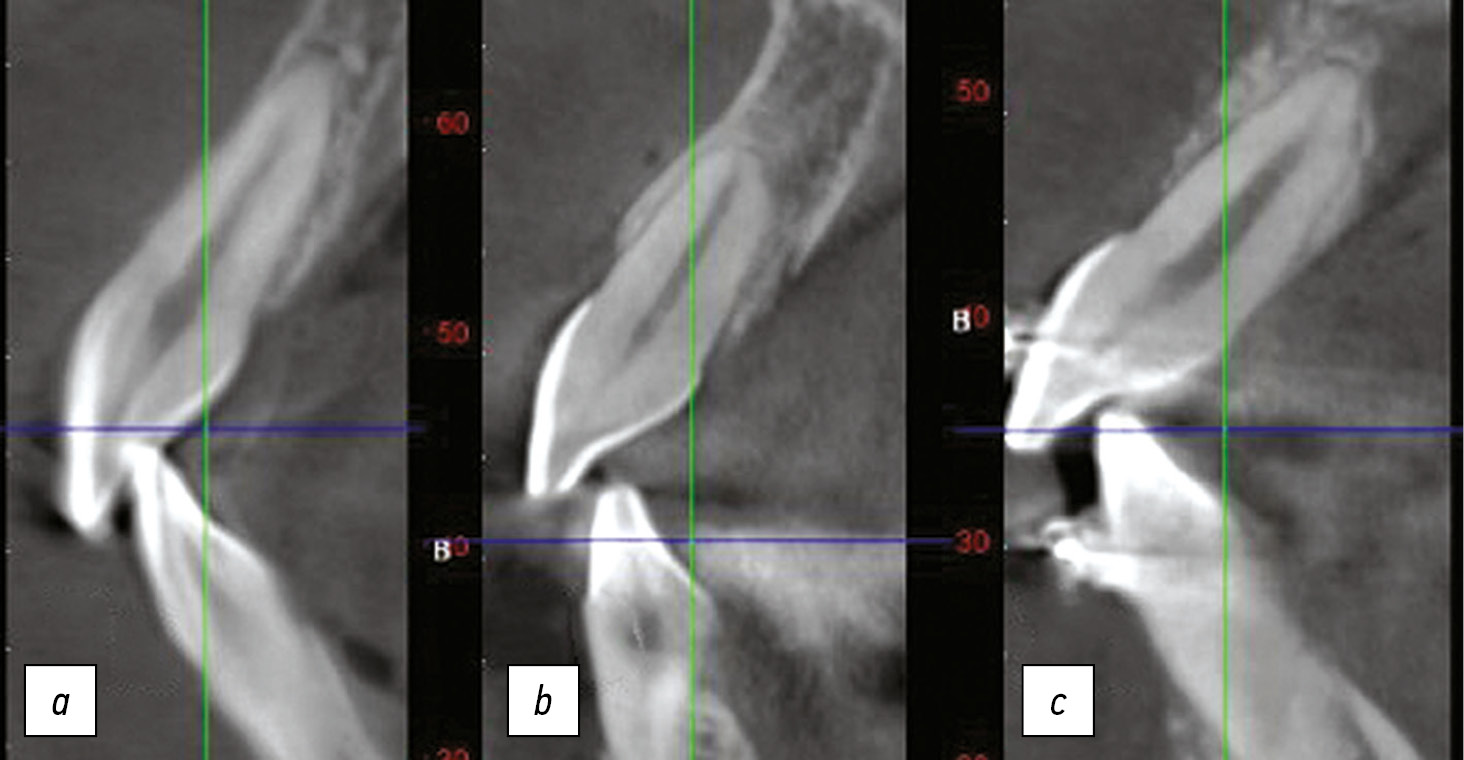

Для проведения исследования пациенты были разделены на 3 группы по 40 человек в каждой, мужчины и женщины от 25 до 45 лет с различным расположением корней центральных резцов верхней челюсти относительно вестибулярной стенки: вестибулярное (В), среднее (С) и нёбное расположение (Н) (рис. 2).

Рис. 2. Расположение корней: а) вестибулярное; b) среднее; с) нёбное.